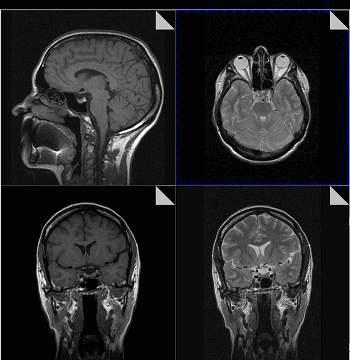

Что показывает МРТ

Магнитно-резонансная томография или МРТ - это сфокусированный метод, который проводит очень детальное обследование. Диагностическая точность МРТ превышает УЗИ и во многих случаях КТ, за исключением сканирования полых органов (легких, желудка, кишечника) и костей. МРТ является золотым стандартом диагностики:

В отличие от быстрого КТ и УЗИ, магнитно-резонансное обследование требует времени - в среднем пациенту нужно лежать в томографе и соблюдать неподвижность 30-60 минут.

Принцип работы МРТ основан на эффекте ядерного магнитного резонанса. МР томограф в своей конструкции имеет мощный магнит, который создает магнитное поле, и датчик, который подает радиочастотные сигналы. В такой ситуации протоны атомов водорода начинают колебательные движения, выделяя при этом импульсы. Их улавливает компьютер томографа и преобразовывает в трехмерные изображения. Чем больше воды содержится в клетках ткани, тем детальней получается ее изображение. Поэтому на МРТ хорошо отображаются органы с большим содержанием воды: МРТ головного мозга, МРТ спинного мозга, МРТ глазных орбит, МРТ органов малого таза, МРТ позвоночника, МРТ суставов, и плохо визуализируются органы с большим содержанием воздуха МРТ органов грудной клетки или кости.

Основы преимуществом МРТ перед КТ и рентгеном является отсутствие в ходе сканирования какого-либо излучения. А вот недостатком этого метода диагностики будет ряд ограничений - наличие ферромагнитного металла в теле пациента и имплантированных в организм водителей ритма, несовместимых с МРТ.

Магнитно-резонансная томография

В основе МРТ лежит явление магнитного резонанса, основанного на переизлучении радиоволн, взаимодействующих с атомами водорода, в избытке содержащимися в организме человека. Эти переизлученные электромагнитные волны улавливаются датчиком МР-томографа, усиливаются и в виде цифровых изображений появляются на экране монитора. Это безвредный и абсолютно безопасный для здоровья человека метод лучевой диагностики, так как в основе получения изображения отсутствует рентгеновское излучение, поэтому МРТ можно проходить неограниченное количество раз, с любым интервалом.

Существенное преимущество МР-томографии перед КТ заключается в том, что она не противопоказана беременным во II и III триместре и совершенно безопасна для детей. В МРТ исследуемая область сканируется в трех проекциях, что позволяет врачу-рентгенологу в полной мере оценить состояние тканей и органов исследуемой области, а высокая контрастность изображения и пространственное разрешение позволяют визуализировать серое и белое вещество головного мозга, оценивать состояние костного мозга и мягких тканей различной локализации. Кроме того, метод МРТ позволяет получать изображения сосудов головного мозга и сосудов шеи без введения контрастного препарата.

Конечно, как и многие другие методы исследования, МР-томография имеет ряд противопоказаний. Однако, если внимательно ознакомиться с ними, можно заметить, что в основном они связаны с наличием металлсодержащих имплантов (не обладающие магнитными свойствами устройства противопоказанием не являются), а также с выраженной клаустрофобией. Таким образом, в большинстве случаев МРТ может стать наиболее оптимальной и совершенно безопасной альтернативой компьютерной томографии и рентгенографии.